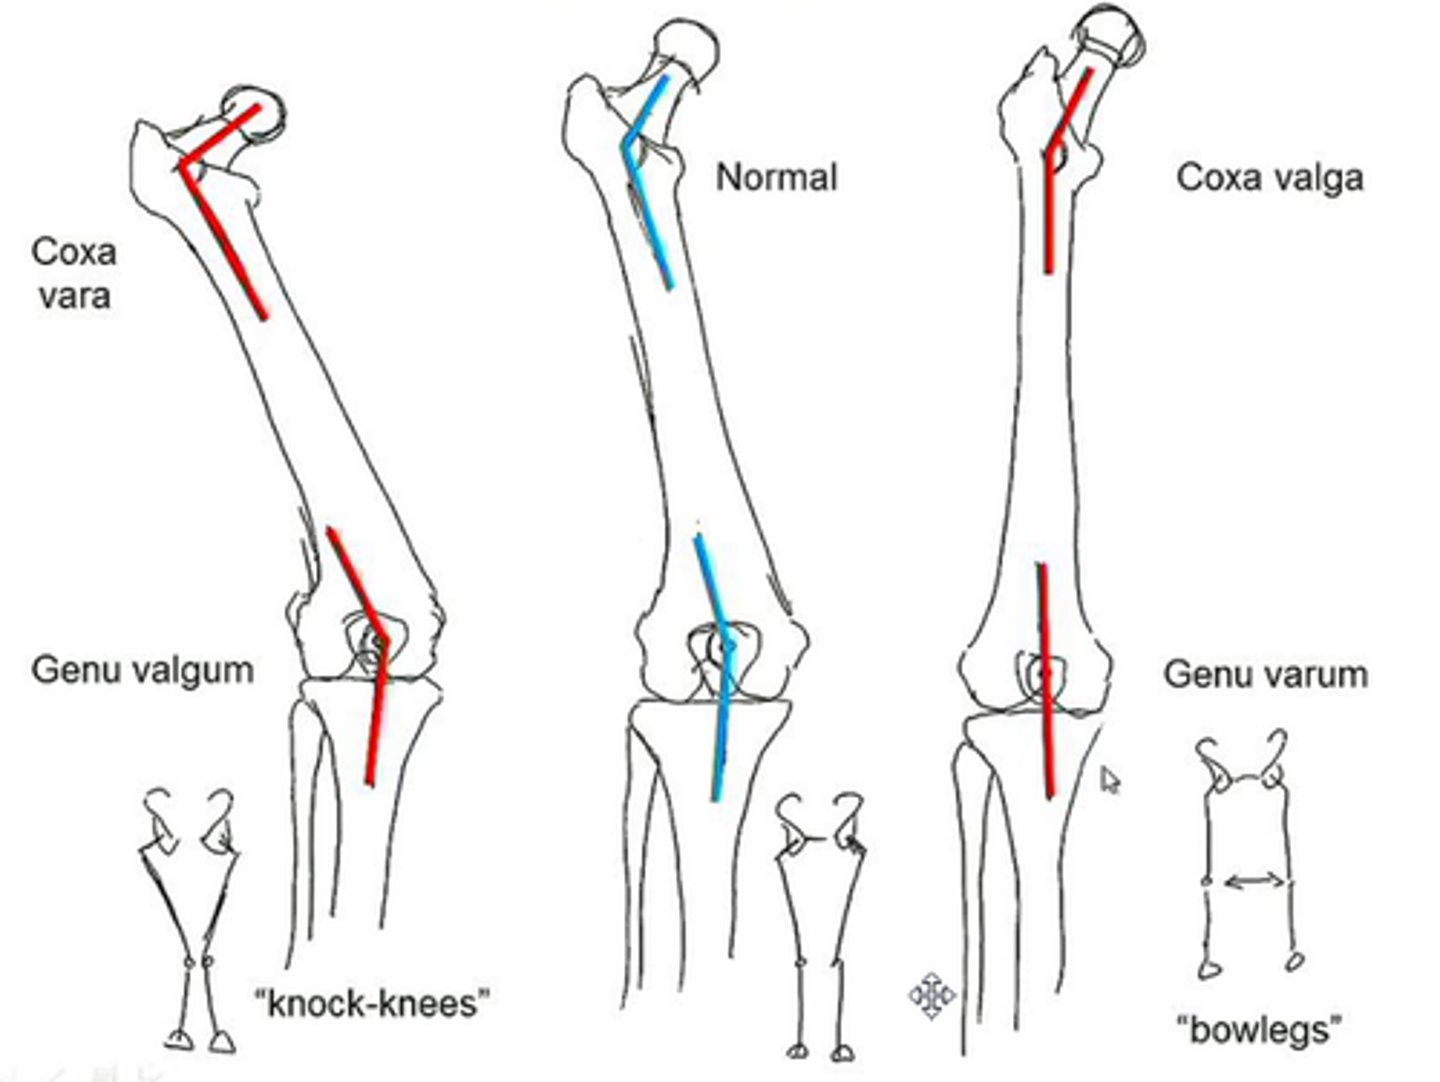

coxa valga

development of femur with angle of inclination GREATER than expected

*involves femoral head/neck and shaft

decrease shear force across femoral neck, increase functional length of abductor m

decrease moment arm of hip abductor (muscle must work harder), less congruency (favors dislocation)

coxa vara

development of femur with angle of inclination LESSER than expected

varum, supinate

valgum, pronate

In an individual with a coxa vara hip, they may experience genu ____________ and therefore _____________ the foot.